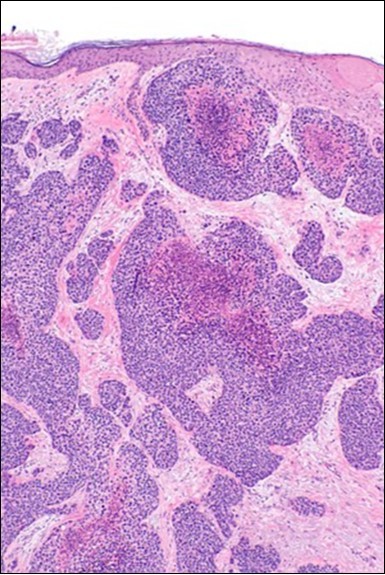

Eccrine porocarcinoma is an infiltrative, high grade tumour which is contiguous with superimposed epidermis, depicts a partially lobular architecture and a diameter usually exceeding > 90 millimetres. An endophytic pattern of tumour evolution is elucidated with invasion of deep reticular dermis and subcutaneous tissue 5, 6.

Eccrine porocarcinoma on morphological elucidation depicts the incrimination of cutaneous structures, foci of ulceration along with multiple areas of cellular infiltration. Tumefaction arises from basal layer of skin.

Classically, intra-epidermal and dermal nests of tumour cells exhibiting cellular atypia and enhanced mitotic activity are enunciated. Tumour aggregates articulate well demarcated, enlarged, atypical polygonal cells with indistinct cellular and nuclear outline, nuclear hyperchromasia , irregular nuclei, vesicular or prominent nucleoli and minimal eosinophilic cytoplasm. Polygonal tumour cells can depict central keratinisation 6, 7.

Granular arrangement of malignant cells and intercellular bridges are conspicuous with the demonstration of nuclear atypia, pleomorphism, prominent mitosis and tumour necrosis. A peripheral palisade is discernible within the cellular aggregates. Mitotic figures are common and can be quantified as up to 12 mitosis/ high power field. Tumour differentiation can prominently be of the ductal category with the demonstration of intra-cytoplasmic lumina. Comedo type tumour necrosis is evident along with foci of squamous differentiation The neoplasm is reactive to periodic acid Schiff ‘s (PAS) stain. (Figure 1, Figure 2, Figure 3, Figure 4, Figure 5, Figure 6, Figure 7, Figure 8, Figure 9, Figure 10, Figure 11, Figure 12, Figure 13.

Figure 4.Cellular atypia, mitosis and focal necrosis in eccrine porocarcinoma(16).